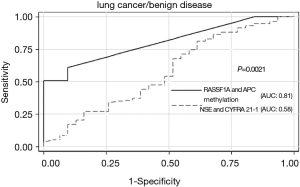

Powers of RASSF1A and APC methylation assay and NSE and CYFRA 21-1 assay in identifying lung cancer from benign disease

To determine the powers of DNA methylation and protein biomarkers (NSE and CYFRA 21-1) in identifying cancer from benign disease, ROC curves were calculated (Figure 3). RASSF1A and/or APC methylation assay had an area of 0.81 under the ROC curve. By using the optimal cutoff value of 150 copies/mL, we got a sensitivity of 56.9% and a specificity of 90.3%. The AUC of CYFRA 21-1 and NSE assay was 0.58, sensitivity of 48.3%, and specificity of 54.8% (using clinical cutoff value). Consequently, the power of RASSF1A and APC methylation assay was superior to that of NSE and CYFRA 21-1 with a P value of 0.0021.

Existing protein biomarkers such as CYFRE21-1 and NSE are lack of high sensitivity, specificity and of limited value for early detection (34,35). The data in our research showed that RASSF1A and/or APC methylation assay has a much higher sensitivity of 56.9% and a specificity of 90.3% than CYFRA 21-1 and NSE assay. Several studies have indicated that hypermethylation of CpG islands in gene promoters can occur early in the progression of lung cancer or can be characteristic of premalignant lesion (36,37). Promoter methylation of p16 has been demonstrated from bronchial basal cell hyperplasia to squamous metaplasia to carcinoma in situ with an increasing frequency of 17%, 24% and 50% respectively (38). The CpG island methylator phenotype status of some TSGs displayed differently between NSCLC and paired normal tissues (39). A newly research revealed that methylation of TSGs could be detected in histological normal lymph nodes of lung cancer patients probably confirmed its role as an early event (40). RASSF1A and APC are TSGs in widely research related to carcinogenesis silenced by promoter methylation. Not only our preview studies but also other researchers have all demonstrated the roles of RASSF1A and APC as key TSGs that involved in epigenetic silencing (41-51).